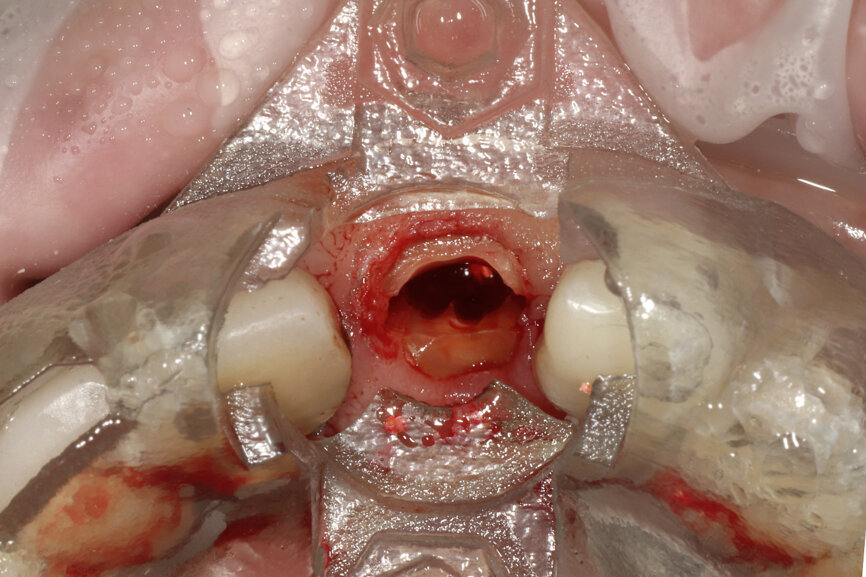

Fig. 22a: The final insert was designed to receive the guided sleeveless drills for accurate osteotomy preparation (a). The osteotomy was prepared to avoid

proximity to the remaining root fragment while leaving sufficient restorative space as previously planned (b).

Prior to the guided drilling, a Gates–Glidden drill was used to remove any gutta-percha within the root. Utilising the tooth-borne template and the first insert, initial long shaper drills (IS1, IS2) were used to reach the apex of the root (Root Membrane Kit; Fig. 17). A periapical radiograph confirmed that the apex length had been reached and that all the gutta-percha had been removed (Fig. 18). The second insert had a metal cylinder that allowed for the long, round diamond drills to shape the root into the desired crescent shape (Fig. 19a). The insert was removed to access the palatal root (Fig. 19b). Using appropriate instrumentation such as periotomes, elvatomes or FRINGS forceps (both TBS Dental), the palatal root was carefully removed (Fig. 20). A periapical radiograph confirmed that the palatal root had been completely removed (Fig. 21). The next insert contained the final diameter to receive the guided sleeveless drills for osteotomy preparation (Fig. 22a). The osteotomy was prepared to avoid proximity to the remaining root fragment while leaving sufficient restorative space, as previously planned in the software simulation (Fig. 22b). Implant placement (AnyRidge, MegaGen) was facilitated by the R2GATE surgical carrier for full-template guidance at the appropriate torque values (Fig. 23). Depth control and rotational positioning were accurately confirmed with the notch indicated on the template to correspond with the insertion tool (Fig. 24).